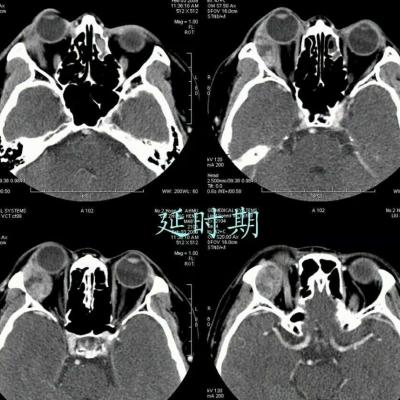

女,54岁,头痛头晕月余,无眼部症状及视力异常。 影像表现:右侧眼球后方占位病变,考虑海绵状血管瘤可能性大,鉴别:视神经鞘瘤、脑膜瘤及炎性假瘤。 病例点评:眼眶内血管瘤是较常见的良性肿瘤,其中以海绵状血管瘤最常见。可发生于任何年龄,主要表现为眼球突出及偏位,在低头或哭泣时可有突眼加重。可经眶缘触及具有压缩性的肿块。视力损害多较缓慢。肿块大多位于肌锥内,其次为肌锥外,平扫呈边界清楚的圆形、卵圆形或分叶状肿块,增强扫描呈缓慢进行性显著强化为其特征性表现。